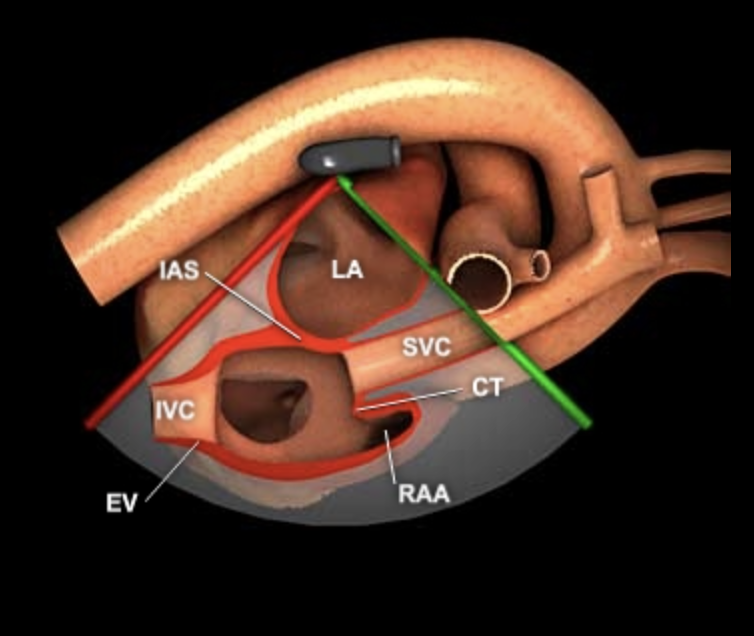

Mid-Esophageal Bicaval View (ME Bicaval)

- Von ME 2C (90°)

- Probe rechts drehen

- Leichte Angulierung/Rotation, um IVC + SVC gleichzeitig zu sehen

- Zielstrukturen:

- IVC + SVC (Drähte/Kanülen/ECMO)

- RAA

- Interatriales Septum